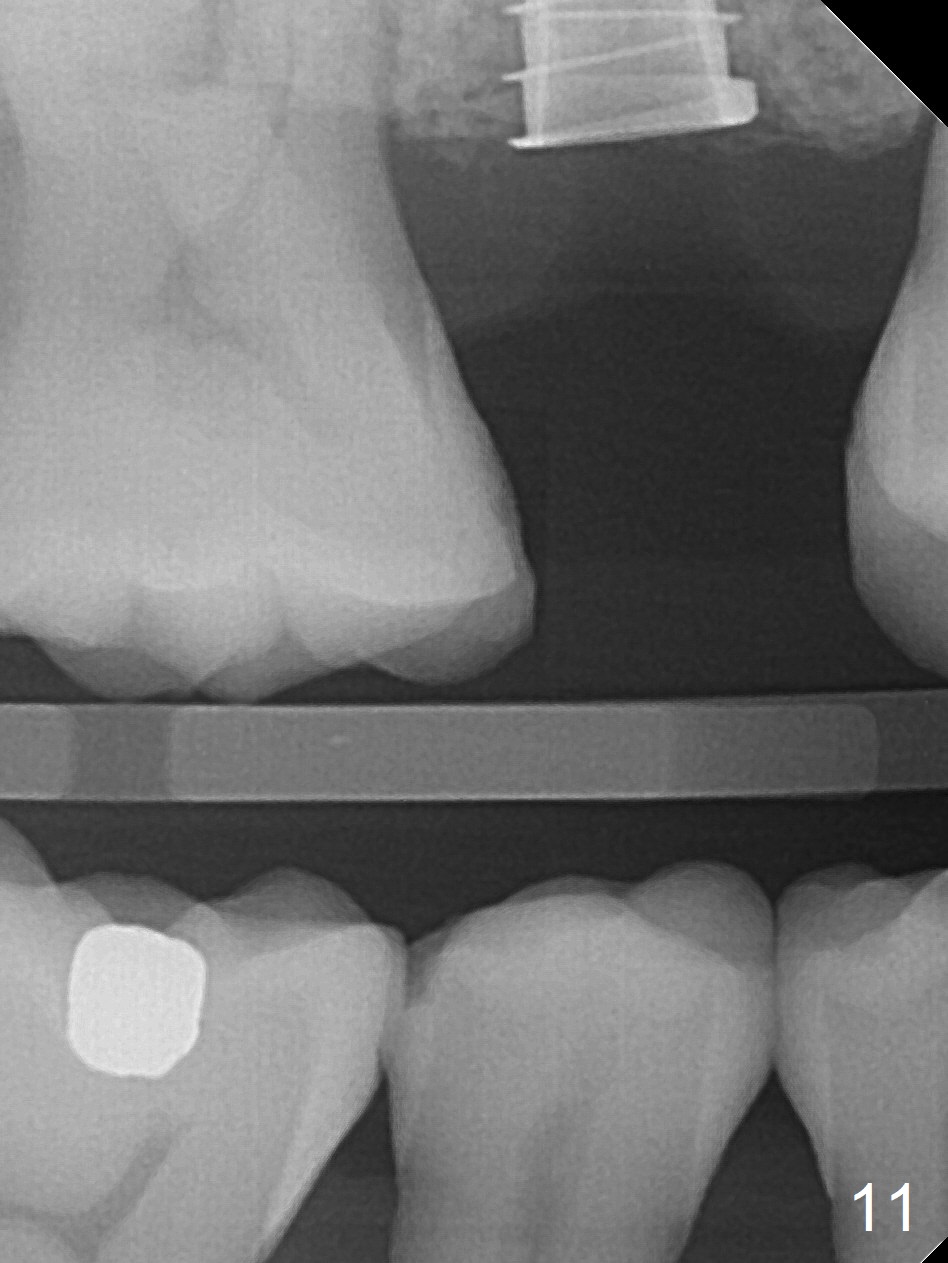

The implant dislodges while the abutment is untightened 8 months postop. The osteotomy is found intact. A 4.5x11 mm dummy implant is placed 2 mm subgingival with 20 Ncm (Fig.9). When a 4.5x11 mm definitive implant is placed 3 mm subgingival (Fig.10,11), torque reaches 50 Ncm. A 5.5x3 mm healing abutment is placed.